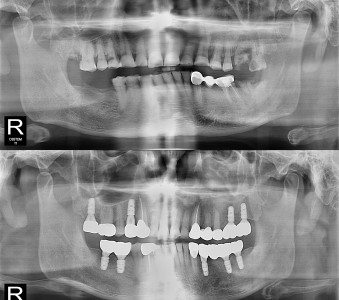

결과로 증명합니다.

국제모아치과의

실제 임상 증례